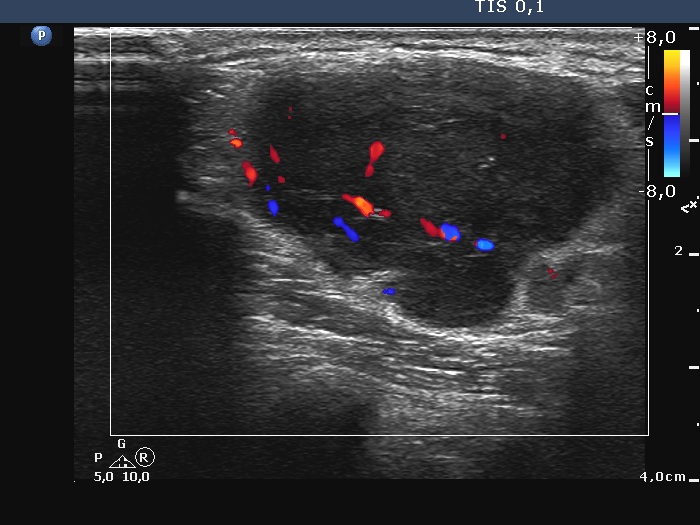

Ultrasonography. The thyroid was echonormal and intact. There was a large and several small lymph nodes in the left supraclavicularegion. The nodes did not have hilum, the largest one presented with irregular margins and irregular vascularity. The diameters of the node were 31x23x45 mm, width, depth, length, respectively.